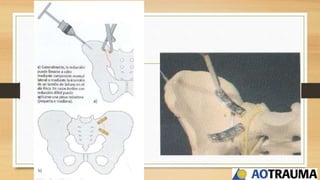

Este documento trata sobre fracturas de pelvis y acetábulo de tipos I y II. Explica la anatomía de la pelvis, incluyendo huesos, ligamentos y vasos. Describe la epidemiología, clasificación y diagnóstico de fracturas de pelvis. Detalla abordajes quirúrgicos, técnicas de osteosíntesis y fijación externa para el tratamiento de fracturas de pelvis. Finalmente, cubre posibles complicaciones.